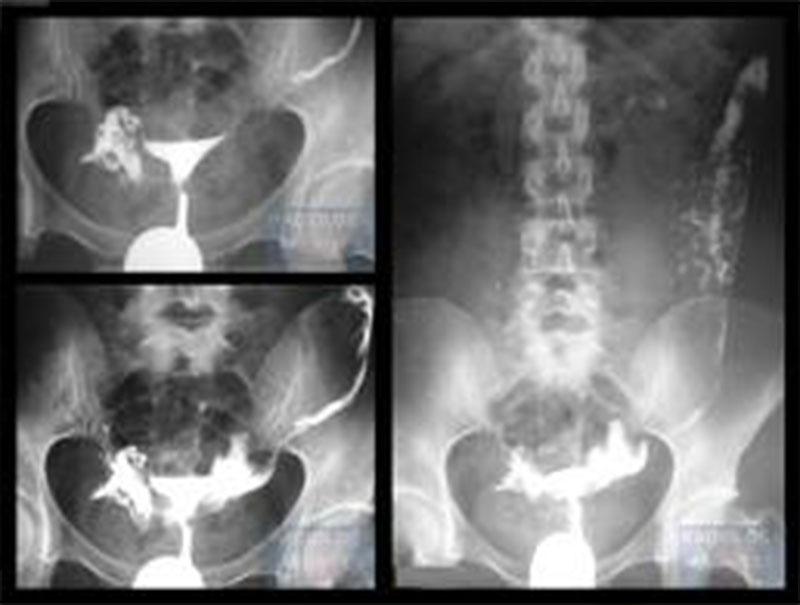

Αρχικά η γυναίκα καλείται να ξαπλώσει σε ένα ειδικό ακτινολογικό τραπέζι κάτω από ένα μηχάνημα ακτίνων Χ. Στη συνέχεια, τοποθετεί τα πόδια της σε στηρίγματα, σαν να επρόκειτο να ακολουθήσει τεστ Παπ. Ένα εργαλείο που ονομάζεται κολποδιαστολέας τοποθετείται στο άνοιγμα του κόλπου, με τη μικρότερη δυνατή ενόχληση. Αφού ο τράχηλος καθαριστεί και προετοιμαστεί κατάλληλα, στη συνέχεια ο εξειδικευμένος ακτινολόγος τοποθετεί ένα λεπτό και μαλακό σωλήνα (καθετήρα) στο στόμιο του τραχήλου. Στη συνέχεια, η σκιαγραφική ουσία ρέει μέσω αυτού του σωλήνα, “γεμίζοντας” με αυτόν το τρόπο τις κοιλότητες της μήτρας και των σαλπίγγων. Κατά το σύντομο αυτό χρονικό διάστημα που οι κοιλότητες “γεμίζουν” με το σκιαγραφικό υλικό (5-10 λεπτά) λαμβάνονται στοχευμένα ακτινογραφίες.

Ο ρόλος του ιωδιούχου υδατοδιαλυτού σκιαγραφικού υλικού, είναι να αποτυπώσει αυτές τις περιοχές (μήτρα και σάλπιγγες) με ακρίβεια στις ακτινογραφίες. Ορισμένες φορές, κατά τη διαδικασία της εξέτασης, η γυναίκα μπορεί να χρειαστεί να αλλάξει θέση προς το Αριστερό ή Δεξιό πλάγιο, προκειμένου να γίνουν καλύτερα κάποιες λήψεις. Συνήθως, ανάλογα βέβαια και με τα ευρήματα, η εξέταση ολοκληρώνεται με μια ακτινογραφία της ασθενούς σε όρθια θέση, προκειμένου να διαπιστωθεί πως το σκιαγραφικό υλικό έχει τελικά περάσει εξ’ολοκλήρου στη περιτοναϊκή κοιλότητα και δεν έχουμε κάποια κατακράτηση υγρού στις σάλπιγγες ( πχ σε περίπτωση συμφύσεων).